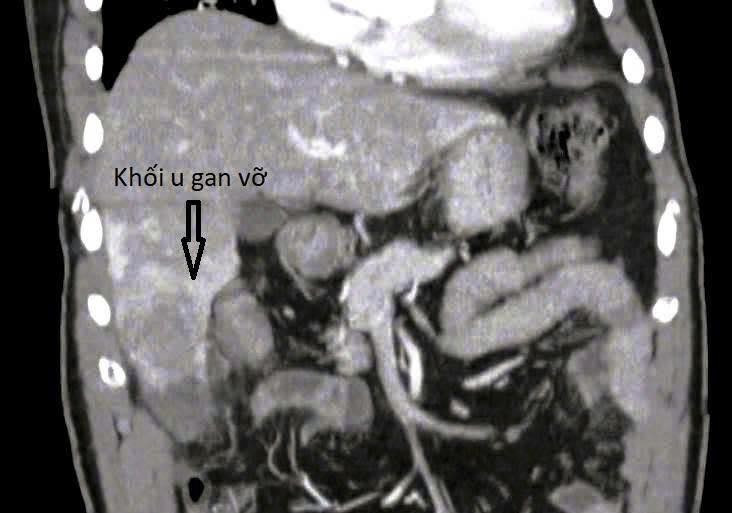

Sau khi thăm khám lâm sàng và thực hiện các cận lâm sàng cần thiết như siêu âm, chụp CT scan, các bác sĩ phát hiện khối u gan ở hạ phân thùy VI, kích thước 73x65x54mm, nghĩ nhiều đến ung thư biểu mô tế bào gan (HCC) trong tình trạng dọa vỡ.

Hình ảnh khối u gan trên phim chụp - Ảnh BVCC